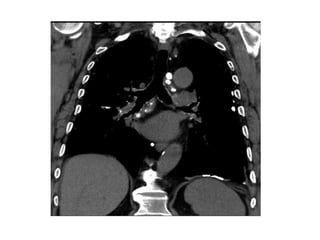

Pneumothorax associated with pulmonary LAM in a 37-year-old

woman, CT image of the chest demonstrates multiple lung cysts,

suggesting pulmonary LAM, pneumothorax can be seen in the right

thoracic cavity (arrows)